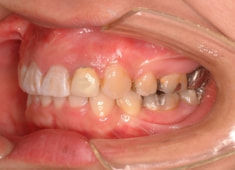

治療前